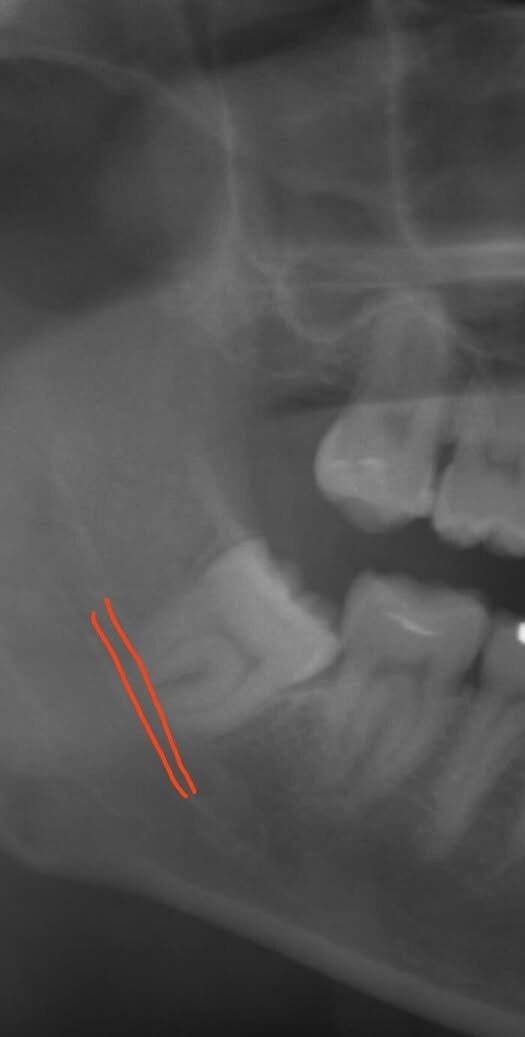

抜歯前

| 治療名 | 親知らず抜歯(難抜歯) |

| 治療内容・説明 | 歯根が開いており先端も太く、下歯槽神経に近接している親知らずの抜歯症例です。手前の歯に食い込んでおり、時々腫れを繰り返していただため抜歯をご希望されました。周囲の歯槽骨を削合してから歯を分割し、慎重に抜歯を行いました。親知らずは骨が硬くなる前の若いうちに抜歯した方が、術後の負担が軽減されます。欧米では将来のトラブルを予防するための早期親知らず抜歯を「ウィズダムトゥースアウト(Wisdom Tooth Out)」と呼び、一般的に行われています。 |

| リスク・副作用 | 抜歯後は腫れ・痛み・出血・内出血(青あざ)が生じることがあります。下顎の親知らずは下歯槽神経に近接しているため、術後に唇や舌のしびれ(知覚麻痺)が生じるリスクがあります。神経に近い症例では、しびれが長期間続く可能性もあります。また、ドライソケット(抜歯窩の治癒不全)により強い痛みが持続する場合があります。術後は安静にし、激しい運動や飲酒、喫煙は控えてください。 |

親知らずの抜歯は、歯の位置や形態、神経との位置関係により難易度が大きく異なります。当院ではCT撮影により事前に詳細な診断を行い、安全な抜歯を心がけています。